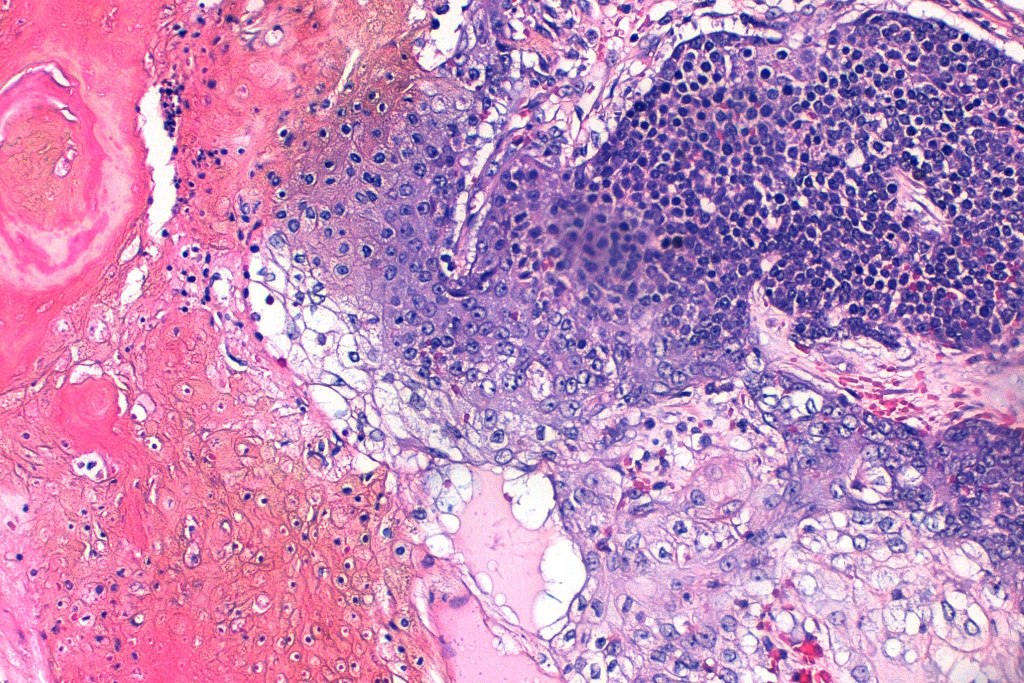

Histological features

•Multilobulated tumor in dermis +/- subcutaneous fat with a fibrous pseudocapsule

•Basophilic small cells which transition towards supramatricial (orange staining) and ultimately ghost cells with intensely eosinophilic cytoplasm

•Intense mitotic activity may be seen in early lesions (this should not be interpreted as implying malignant potential)

•No abnormal mitoses or pleomorphism

•Late features include calcification and bone formation

•Foreign body reaction